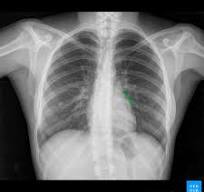

3.4 Identifying pneumonia from chest X-rays

![]() |

|

| (a) | (b) |

Chest X-rays (CXRs) are a widely-used diagnostic tools, used to identify various lung or heart conditions. There are approximately 70 million CXRs performed within the United States each year [iyeke2022reducing], so automated procedures for identifying occurrences of a given health condition based on a CXR could dramatically improve the overall workflow and efficiency of hospitals. However, high-quality labeled data is difficult to obtain, since it requires the time and effort of a radiologist. In recent years, researchers have turned towards synthetic labels derived from natural language processing (NLP) systems [irvin2019chexpert, peng2017negbio], but these labels are very “noisy” relative to the ground truth. At the same time, the noisy labels provide a natural choice of helper covariate for the PAST procedure.

Concretely, we studied the binary classification problem of predicting, on the basis of a CXR, whether or not the patient has pneumonia. It is a lung infection that causes air sacs to fill with fluid, inhibiting breathing; see Figure 4 for comparison of a healthy CXR to one indicating pneumonia. In order to do so, we used data taken from the MIMIC-CXR database [johnson2019mimiccxr]; it consists of a collection of CXRs that are each paired with a radiologist report. As our helper covariate, we made use of synthetic labels from the NegBio procedure; these are noisy labels, in the sense they had roughly disagreement with the radiologist’s labels.